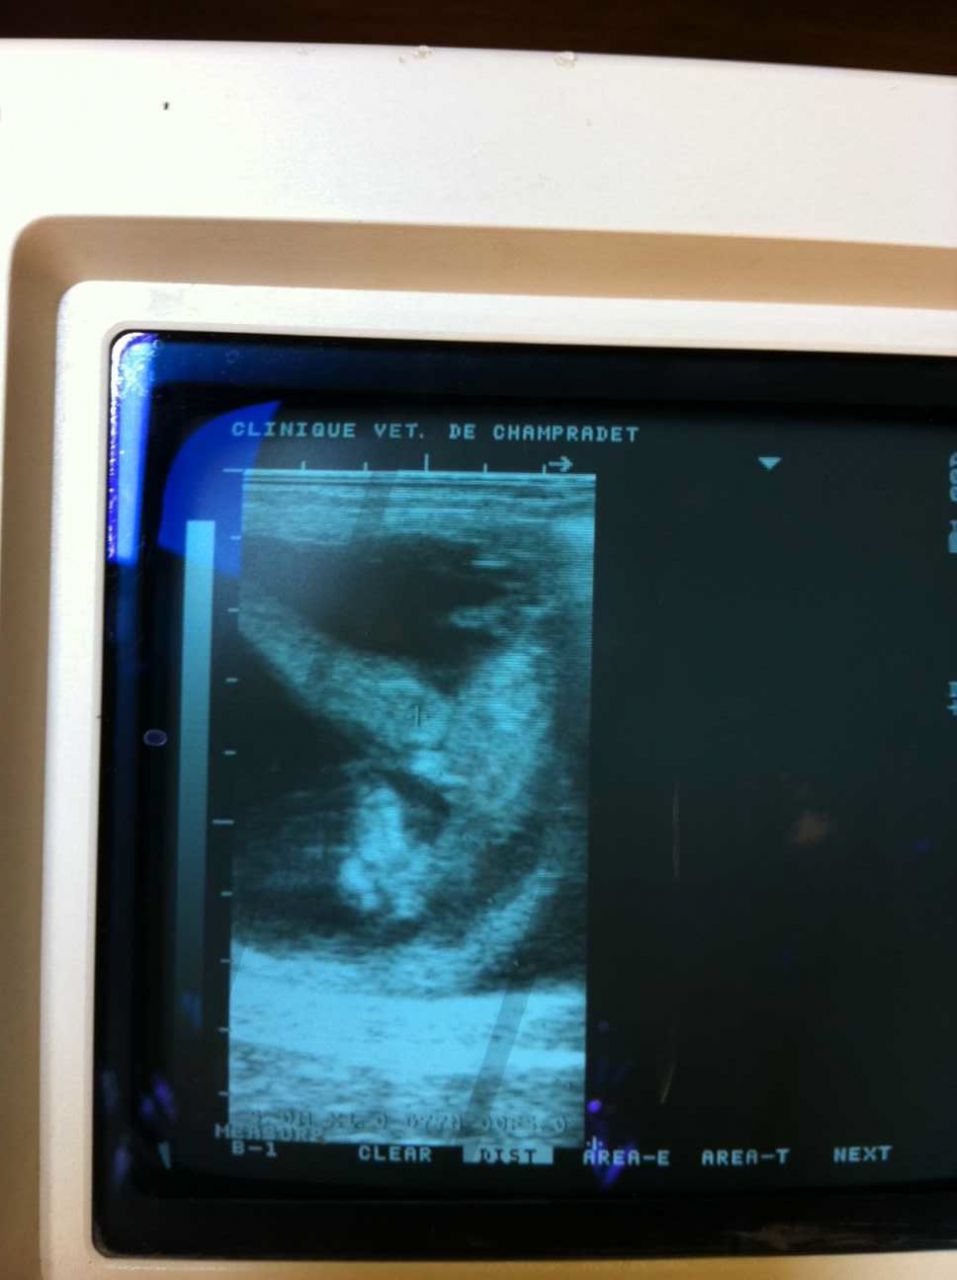

Par majaffi : le 02/07/11 à 10:59:48

| Dire merci | Ca y est la dernière écho a été faite ce matin pour Ottawa. Tout le monde va bien. Une petite photo du futur poulinou : ![]() Il est tourné, la tête est en bas encapuchonnéé. Il est pas franchement beau car sa tête fait la même taille que le ventre, mais il bouge super bien. Le véto m'a même dit que d'ici 15 jours on aurait pu voir le sexe, (aujourd'hui on a juste vu l'appareil génital). Mais bon comme de toute façon, il n'y aura plus d'écho Plus qu'à le garder bien au chaud jusqu'en avril prochain Message édité le 02/07/11 à 11:02 |

| Dire merci | majaffi : le poulain a quel age sur la photo ?? J'ai une photo de l'écho à 1 mois on ne voyait pas du tout ca, juste une boule au milieu La véto avait fait un arrêt sur image et j'avais pu prendre la photo après que l'écho soit finie Désolée makiro ![]() |

Par majaffi : le 03/07/11 à 09:02:07

| Dire merci | Oh ben merde makiro, c'est la galère !!!!!![]() Paulyneee : le poulain a un mois et trois semaines, sur l'écho. Là il était particulièrement bien positionné apparemment ! ![]() |